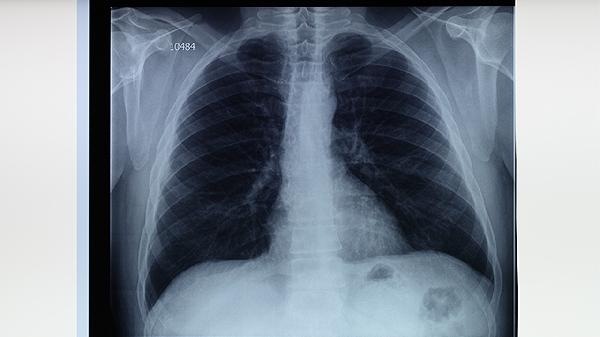

除上述三种因素外,还可能与支气管扩张、肺脓肿、肺癌等因素有关。具体原因不能仅仅通过一个体征来判断。建议先就医进行痰检和影像学检查,明确病原体的具体类型和原因,然后对症选择合适的治疗方案。在呼吸道疾病的治疗过程中,要注意劳逸结合,避免吃辛辣刺激性食物。